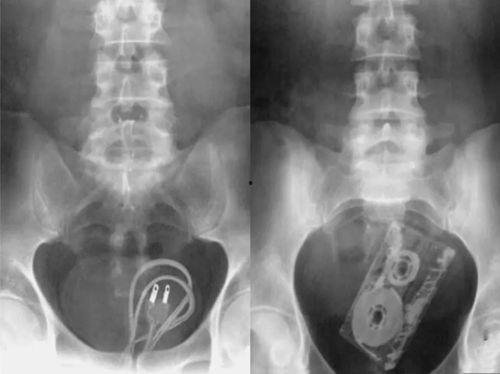

泌尿肛肠吃瓜,揭秘“吃瓜群众”的健康隐患 最近在网络上可是掀起了一股“泌尿肛肠吃瓜”的热潮呢!这可不是普通的瓜,而是关于健康的小秘密,让人忍不住想要一探究竟。咱们就来聊聊这个话题,看看这些看似平常的部位,背后隐藏着哪些有趣的知识吧!一、泌尿系统:健康的小卫士... 娱乐头条 admin 26-01-26 16 0